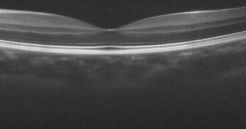

The effect of the overlap of the patches on the final output of the algorithm has been investigated in the next simulation. For this purpose, the outputs of the proposed approach for the situations and have been compared. When , the patches have no overlap. The resulting higher resolution OCT images for each situation have been illustrated in Fig. 8. Visual comparison in addition to the PSNR and SSIM for each image, show that using patches with overlap, we can increase the performance of the algorithm and consequently improve the quality of the output image.

Reference image

Using patches without overlap

Using patches with overlap